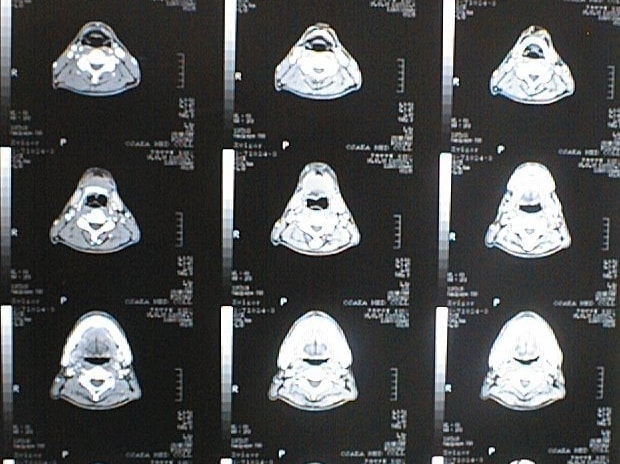

中咽頭末期がんCT画像②

入院当時CT画像②

中咽頭末期がん消滅CT画像②

入院3か月後癌消滅CT画像②

中咽頭末期がんCT画像③

入院当時CT画像③

中咽頭末期がん消滅CT画像③

入院3か月後癌消滅CT画像③